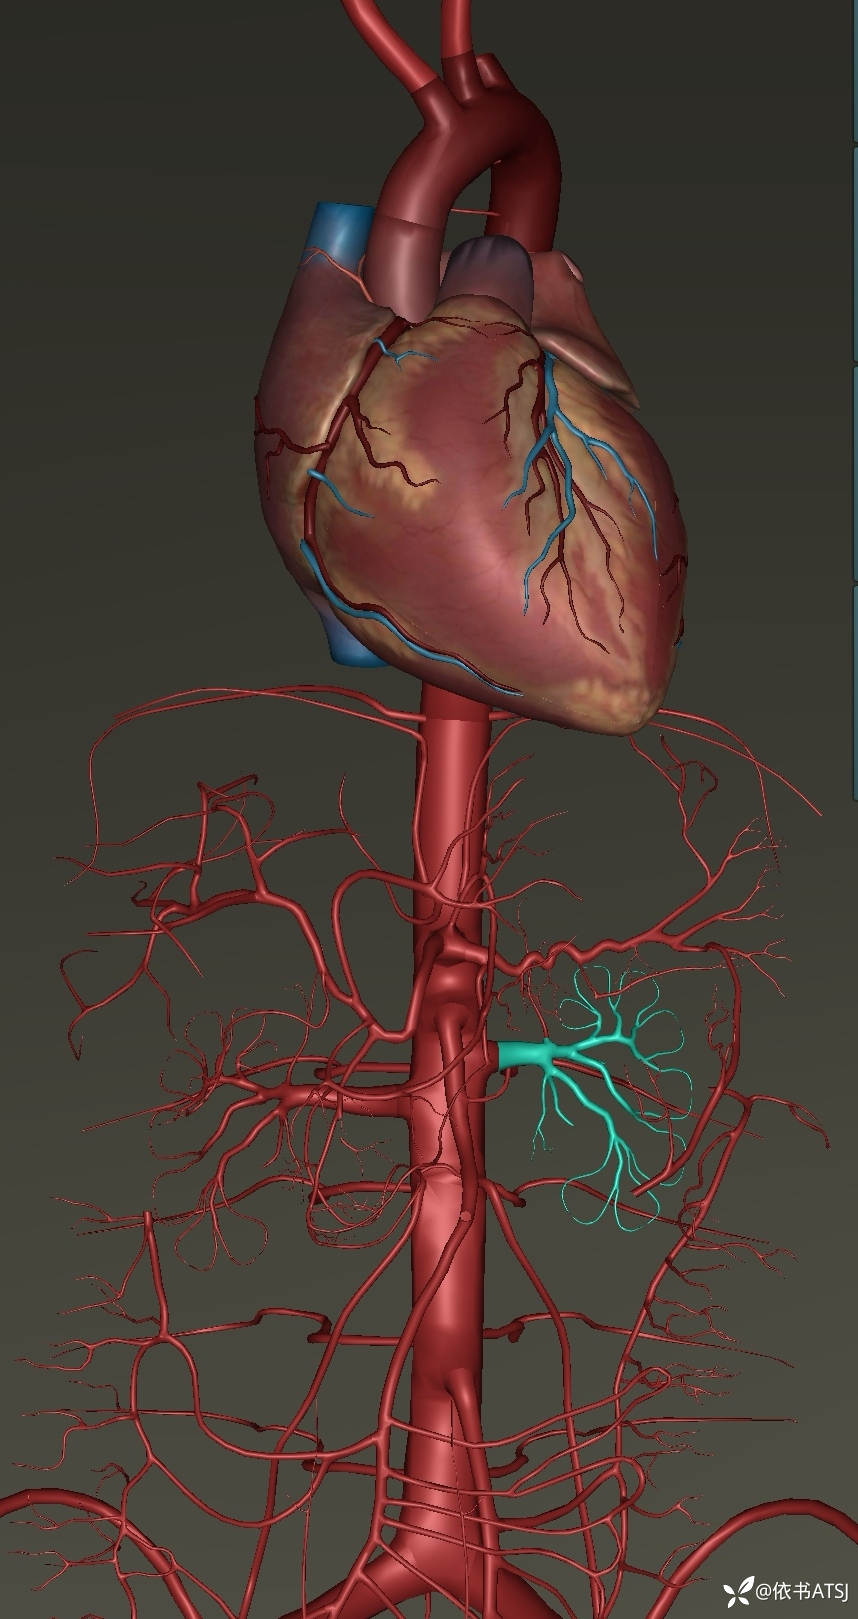

升主动脉-腹主动脉全程增粗,多个破口,累及肠系膜动脉、髂总动脉、髂内髂外动脉

讨论:本例患者,34岁,体型肥胖,高血压3年余,未重视,未系统诊治,突发胸腹部疼痛入院,虽然放了根长长的支架,命保住了,尿量也不错,可是血肌酐高,短期内脱离不了透析,针对这一年轻患者的全程广泛主动脉撕裂、多个破口,各位老师,您认为非常有必要排查血管炎这一疾病吗?